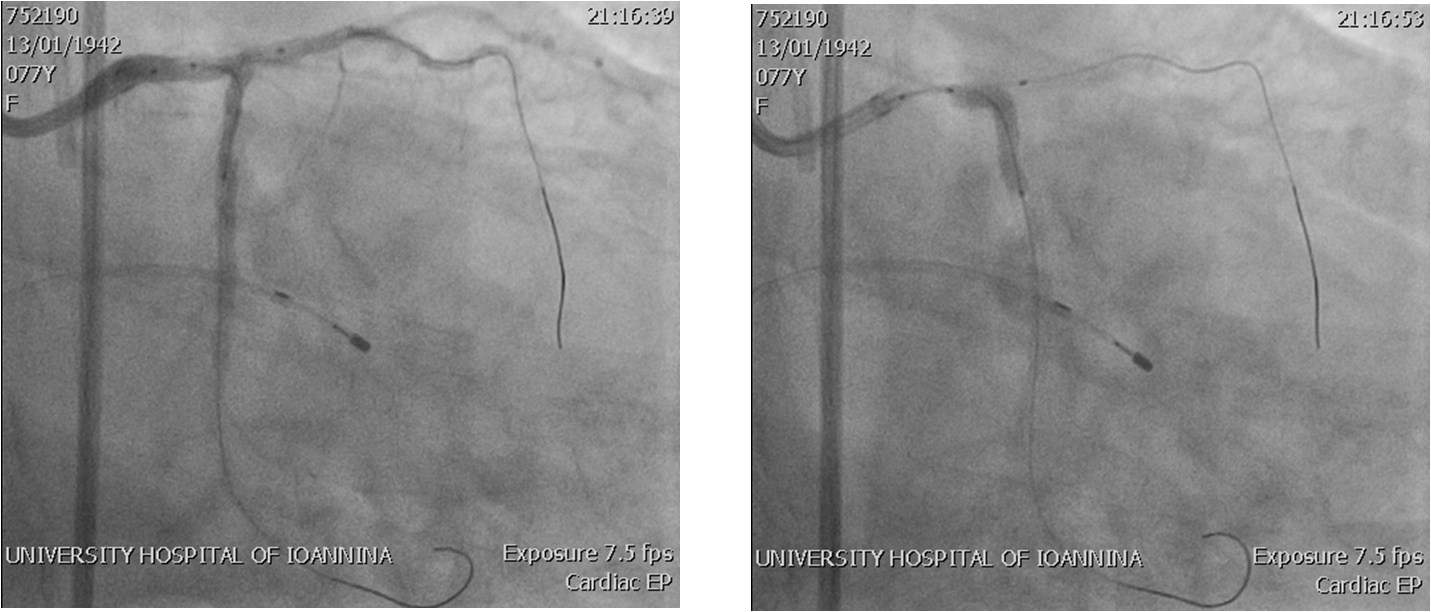

Αγγειοπλαστική αριστερής στεφανιαίας αρτηρίας (LM/LAD/LCx)

- Αγγειακή πρόσβαση και προετοιμασία στο αιμοδυναμικό εργαστήριο – Τοποθέτηση ενδοαορτικού ασκού (IABP) και προσωρινού βηματοδότη (TPW)

- Αγγειοπλαστικη – Βήματα: Rotablation & DK-crush PCI

- Rotablation LM-LAD

- Pre-dilations (Kissing)